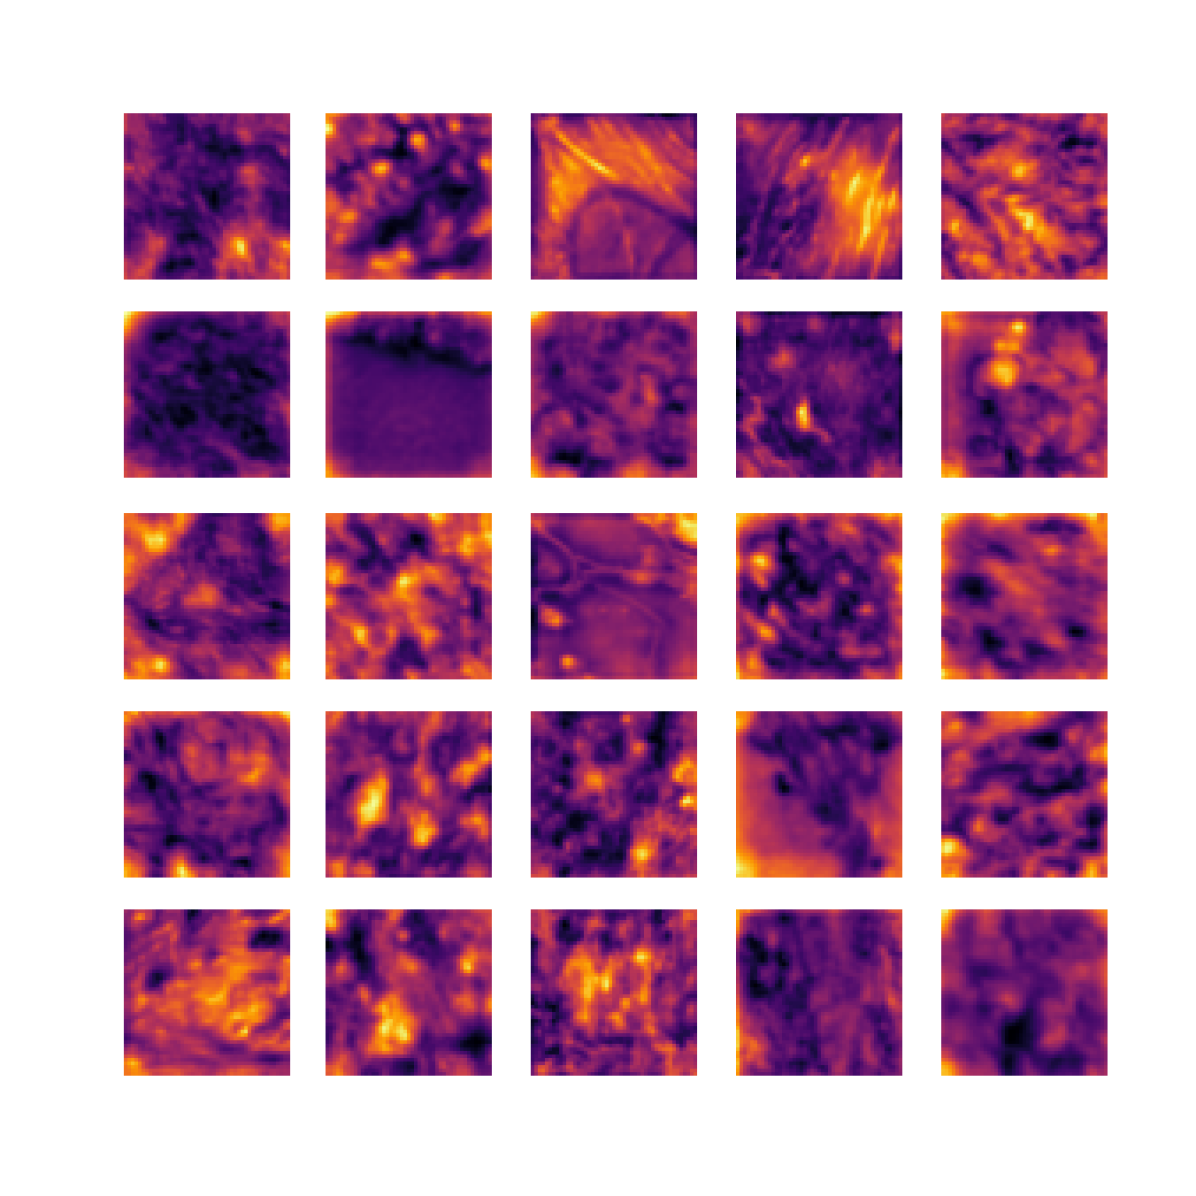

We also analyse the activation maps for each model using GradCAM as described in section S3. This offers more insight into the areas of the image which are contributing most heavily to the models’ representations. In Figure 4(b) we present some representative examples, however, a larger selection which was chosen at random is presented in Figures S10 to S25. The larger selection makes it easier to see the emergent patterns, including that privileged Siamese models tend to mainly identify features which are strongly present in both inputs, while unprivileged Siamese models tend to learn more diffuse features that are not specific to one cell phenotype or image region. TriDeNT ♆ incorporates both sets of features, learning both features specific to the privileged data and more the general features associated with unprivileged Siamese networks.

We can see in Figure 4(b) panel A that for ERG, the privileged Siamese model focuses almost exclusively on any nuclei which could be endothelial cells. As there are very few endothelial cells in the dataset, it could be an effective strategy to identify anything that could potentially be an endothelial cell to minimise the difference between the representations of the H&E model and the IF mask model. In the corresponding unprivileged Siamese image, we see that the model identifies some of these nuclei, albeit less strongly, but also focuses heavily on the other tissue and even the background, while strongly fixating on two spots of debris in the center of the image. This model has less ‘incentive’ to learn the weak features related to endothelial cells as these occur rarely and are not easy to detect, while more generic strong features such as the presence of connective tissue and the prevalence of background are more common and predictable from augmented images. We see that TriDeNT ♆ combines these two feature sets, strongly identifying nuclei while also identifying the connective tissue.

In panel C we see a similar pattern, with the privileged Siamese model fixating solely on the nuclei, while the TriDeNT ♆ model takes a more balanced approach. The unprivileged Siamese model appears to focus on a single cluster of nuclei while neglecting others, and similarly identifies an area of fibroblasts with its distinctive pattern but does not others.

In contrast to panels A and C which represent models with poor privileged Siamese results, panels B and D represent models whose privileged Siamese results were comparable to both TriDeNT ♆ and even the supervised baseline. It is therefore interesting to note that there are far more similarities between the privileged Siamese and TriDeNT ♆ models in both cases. Particularly in panel B, TriDeNT ♆ and the privileged Siamese model return virtually identical heatmaps, with both strongly identifying epithelial nuclei and neglecting the same areas of connective tissue. The unprivileged model in this case appears to focus solely on the centre of the image, giving a significantly different heatmap to the other panels.

Panel D again shows the previous pattern, with the privileged Siamese model identifying the features strongly present in the privileged data – fibroblasts – while neglecting the nuclei present. TriDeNT ♆ also strongly identifies the connective tissue, but, unlike the privileged Siamese model, does not completely neglect the nuclei. The unprivileged Siamese model primarily identifies background, and does not appear to identify the nuclei in this example.